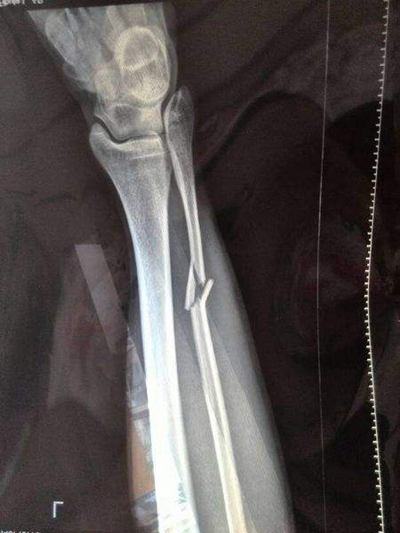

骨折圖片

A:腓骨是人體中小腿骨中比較細的一根骨骼,它的負重比較少,一般腓骨近端的骨折都伴有脛骨的骨折,也可能伴有踝關節的骨折。單純的腓骨近端骨折一般不需要手術,腓骨的近端有腓總神經纏繞,離腓總神經非常的近,所以如果手術的話很容易損傷腓總神經,造成足下垂……